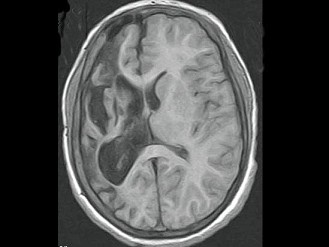

男,35岁,有颅脑外伤史,MRI图像,最可能的诊断是()

• A.脑软化

• B.脑萎缩

• C.脑积水

• D.脑穿通畸形囊肿

• E.脑实质占位